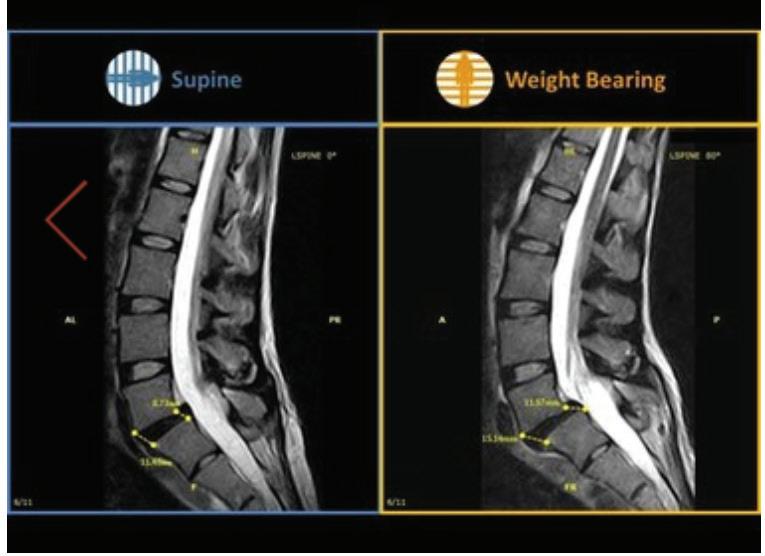

What a weight-bearing MRI reveals vs. a Supine MRI

G-scan Brio Reveals What Supine MRI Misses

Conventional MRI may not demonstrate the pathology related to these symptoms, but G-scan Brio gives you a new point of view so you can accurately diagnose MSK pathologies affected by weight-bearing position.

More Detail, Better Accuracy, Greater Confidence

G-scan Brio: Adds Weight To Your Diagnosis

The G-scan Bro is superior to other MRIs because both the magnet and patient can rotate from 0 to 90 degrees.

G-scan Brio offers a revolutionary MRI approach that increases diagnostic accuracy and confidence for musculoskeletal applications.